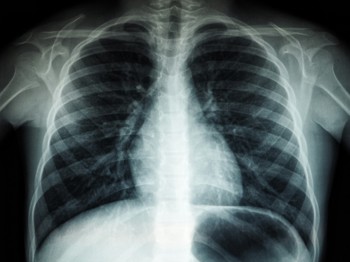

The Cheshire and Merseyside Radiology Imaging Network (CAMRIN) is helping clinicians to detect lung cancer more quickly with the rollout of new AI technology to support the diagnosis of lung cancer.

£1.2m was awarded to Cheshire and Merseyside from the AIDF to accelerate the implementation of an AI imaging and support tool which can analyse chest X-ray images and identify possible signs of lung cancer.

The technology is supplied by Annalise.ai a global health company offering AI solutions for clinicians. Annalise.ai’s technology uses AI to facilitate fast, accurate detection of up to 124 clinical findings and act as a second pair of eyes for clinicians helping them to ensure an accurate diagnosis of lung cancer patients more quickly.

Initial feedback from CAMRIN users has been very positive with clinicians recognising the value of detection capabilities and the many benefits that the new technology will provide to patients. When the AI technology identifies a potential lung cancer case, the information is relayed to the radiologist in under a minute. If they confirm the solution’s findings, the patient is booked for a CT scan on the same day, fast tracking both diagnosis and treatment.